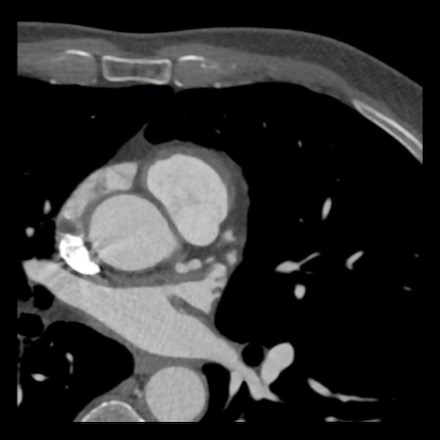

case 2 – CAD-RADS 5/P2/S

First, scroll through the CTA images.

How would you describe the findings on the coronary CTA?

The findings are:

- Stent in the mid

LAD with low-attenuation within the stent suggestive of minimal in-stent

restenosis (<25%). Non-calcified plaque distal to the stent

causing mild stenosis (25-49%). Notice bridging on a short segment in

the distal LAD. - Non-calcified

plaque in the LCX causing mild stenosis (25-49%). - Occlusion of the

proximal OM1 branch with distal filling. - Calcified and

non-calcified plaques in the proximal RCA causing mild (25-49%) stenosis. - Total plaque burden

is moderate based on SIS (four segments including proximal RCA, mid LAD, prox

LCX and OM1).

Due to the occlusion of OM1 branch and presence of the stent, this case

reads as CAD-RADS 5/P2/S, which means that this patient needs further

diagnostic workup.